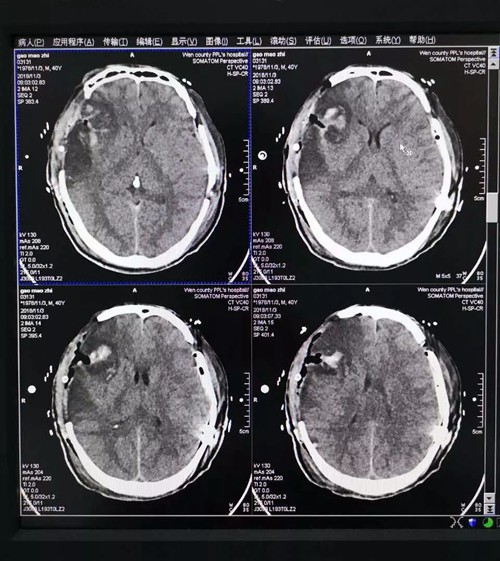

11月2日,由我院副院长杜敏带队一行6人赴文县第一人民医院开展健康义诊工作,尹卫宁教授应邀参与此次活动。活动期间,尹教授开展了一例左侧硬膜外血肿清除术、右侧去骨瓣减压脑内血肿清除术,手术过程顺利,挽救了患者生命。术后复查CT,患者恢复良好。

术后患者复查CT